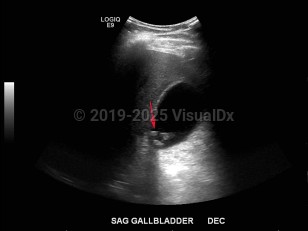

Biliary calculus

Treatment depends on size, location, and symptoms. Gallstones may end up in the duodenum or pylorus, which may result in gastric outlet obstruction (Bouveret syndrome). Common treatments are stone removal by endoscopic retrograde cholangiopancreatography, sphincterotomy, biliary stenting, and cholecystectomy. Goals of therapy are to prevent recurrent episodes of biliary colic and lower the risk of developing choledocholithiasis, cholangitis, and gallstone pancreatitis.